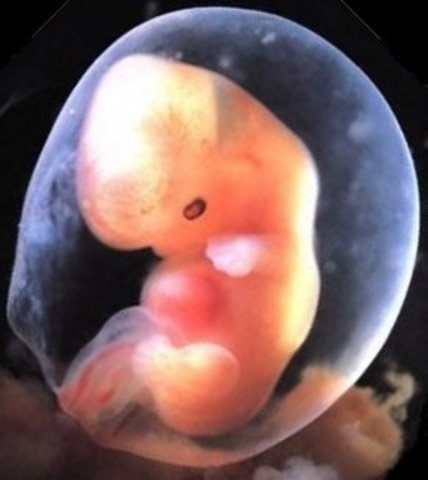

The embryo's arms and legs begin to grow from the buds at each side. The baby's eyes and inner ears also start to develop.

The arms and legs continue to develop while the hands and feet begin to form. The mother will begin to feel the baby moving at week 20.

The arms and legs have lengthened. Their fingers and toes are forming, but are webbed.